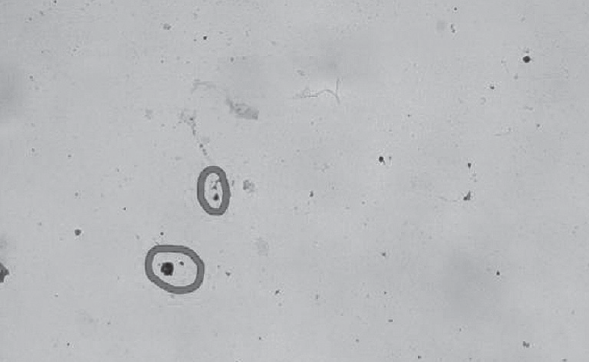

Материалы и методы. Под наблюдением врачей-педиатров отделения материнства и детства Санкт-Петербургского Центра СПИД находилось 388 ВИЧ-инфицированных детей в возрасте от одного месяца до 17 лет включительно. Объектом иммуногистоцитохимического исследования явились отобранные методом случайной выборки ВИЧ-инфицированные дети, обратившиеся в центр по профилактике и борьбе со СПИДом на повторные обследования. Материал для исследования на наличие антиген ВИЧ-1 р24 отбирали с задней стенки носоглотки.

Результаты. При анализе путей инфицирования ВИЧ детей, состоящих на диспансерном учете в отделении материнства и детства Санкт-Петербургского Центра СПИД, оказалось, что 363 ребенка были инфицированы перинатально (93,6 %), 23 (5,9 %) заразились половым путем и 2 ребенка через инъекционные наркотики (0,5 %). По причинам позднего выявления и ВИЧ-диссидентства родителей среди детей, наблюдающихся в СПб Центре СПИД, кумулятивно умерло 18 детей (4 %). Предложенный иммуногистоцитохимический метод для диагностики ВИЧ-инфекции у детей может найти свое применение, особенно для первичной лабораторной диагностики, что, возможно, упростит и удешевит этот процесс.

- Moonim MT, Alarcon L, Freeman J, et al. Identifying HIV infection in diagnostic histopathology tissue samples – the role of HIV-1 p24 immunohistochemistry in identifying clinically unsuspected HIV infection: a 3-year analysis. Histopathology. 2010;56(4):530-541. https://doi.org/10.1111/j.1365-2559.2010.03513.x.